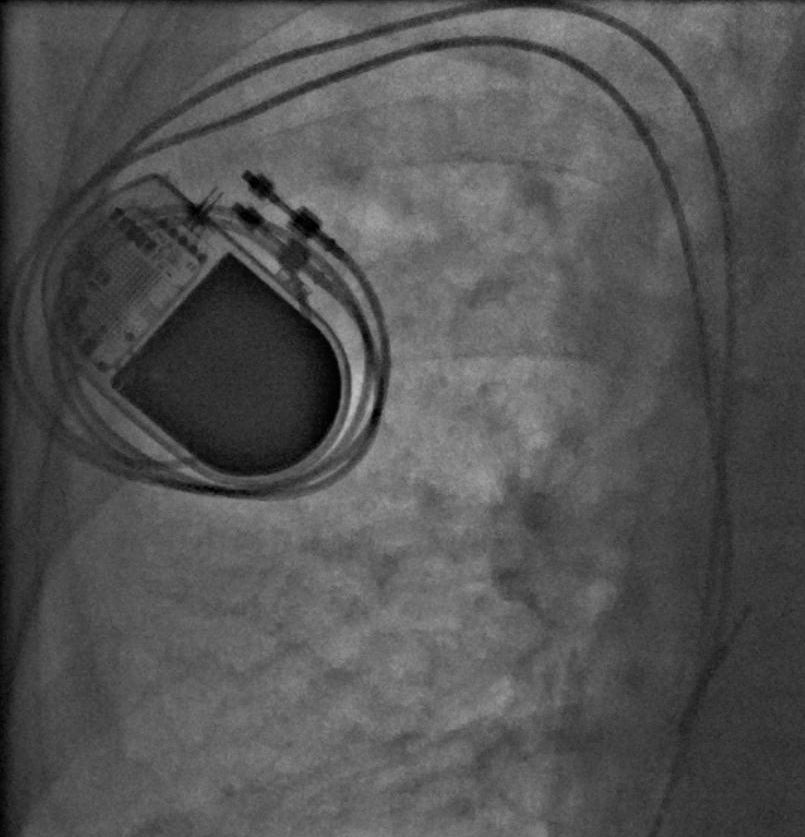

二、埋藏式永久心臟起搏:對(duì)于慢性心律失常、心衰等疾病,可以用各種各樣的起搏器,模仿生理起搏,滿足心臟病患者個(gè)性化治療需求。

四、心臟再同步化治療(CRT/CRT-D植入)頑固性心力衰竭。